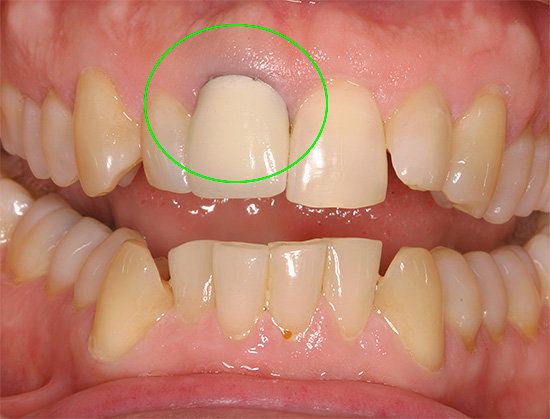

Também é perigoso suportar dor de dente sob a coroa (especialmente se a dor aparecer repentinamente sob uma coroa instalada há muito tempo). A presença de sensações desagradáveis aqui indica o desenvolvimento de um processo patológico oculto, cuja escala só pode ser avaliada na imagem da clínica. A situação é semelhante quando um dente dói sob um recheio (estabelecido há muito tempo) - nesses casos, o problema não pode ser resolvido em casa, é necessária uma visita obrigatória ao médico.

Se o dente dói sob a coroa, pouco pode ser feito em casa - nenhuma loção e receita folclórica costuma ajudar. Na melhor das hipóteses, a inflamação da gengiva pode ser aliviada.